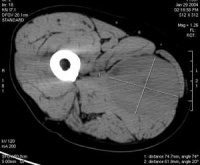

影像学检查:一般无典型的放射学特征,通常无钙化现象。肿瘤可侵蚀并破坏邻近骨质,尤以颅骨、前臂、手部和足部多见。应用加造影剂的CT和MRI检查,可较好地显示肿瘤的部位、体积、边缘及其与周围组织的关系。静脉肾盂造影可发现膀胱内不规则充盈缺损、肾盂积水等。其它的检查方法包括骨扫描(疑有骨转移)和淋巴管造影(疑有淋巴结转移)。

肿瘤好发于眶上部,尤其鼻上象限眼睑处,也可发生在球后或眶内任何部位,约一半位于哐上方者有上睑表现为急性发病,眶缘部肿块可在短期内迅速增大,很快发展为单侧突眼,结膜水肿,上睑下垂,皮肤充血、肿硬,伴发热,可误诊为眶蜂窝织炎。如肿瘤侵及视神经和眼外肌,则视力丧失,眼球运动障碍。如不及时治疗,肿瘤可蔓延整个眼眶,累及鼻窦,甚至进入颅内。立即进行CT、MRI和B超等影像检查,能明确肿瘤的部位和范围,CT检查在儿童如显示眶骨破坏则有助于确诊。如临床诊断不明确,可作活检病理诊断。此外,应体检耳前、颈淋巴结有否局部转移。